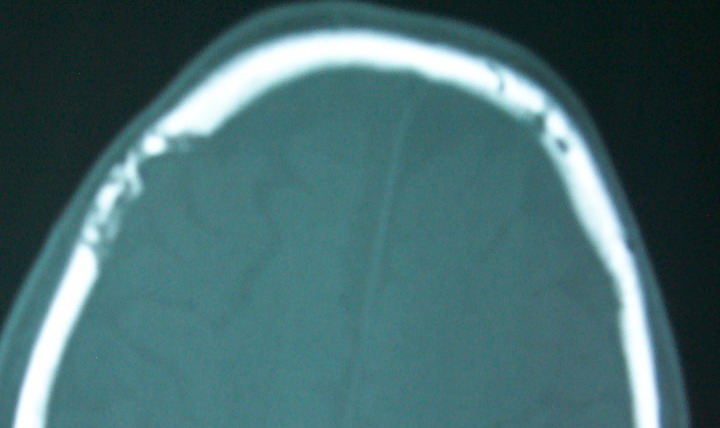

以下是引用余辉在2009-4-15 20:49:00的发言:[br]右侧病灶发生于冠状缝区,但额骨左侧鳞也有病灶,病灶区脑沟裂增宽(有脑萎缩征像,把这个征像放在颅骨病变一起考虑可能有点牵强),是否可能是板障血管畸形所致谢?抑或是嗜酸性肉芽肿或蛛网膜粒压迹那类东西?

以下是引用whzht在2009-4-15 20:57:00的发言:[br]1、额骨改变,考虑蛛网膜粒压迹;[br]2、脑萎缩。